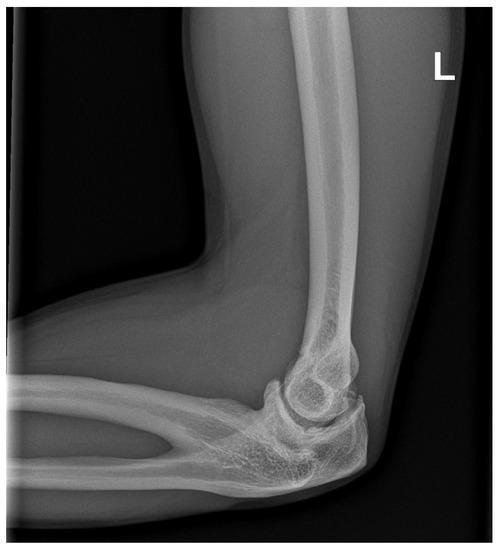

2.2. Radiographic Evaluation